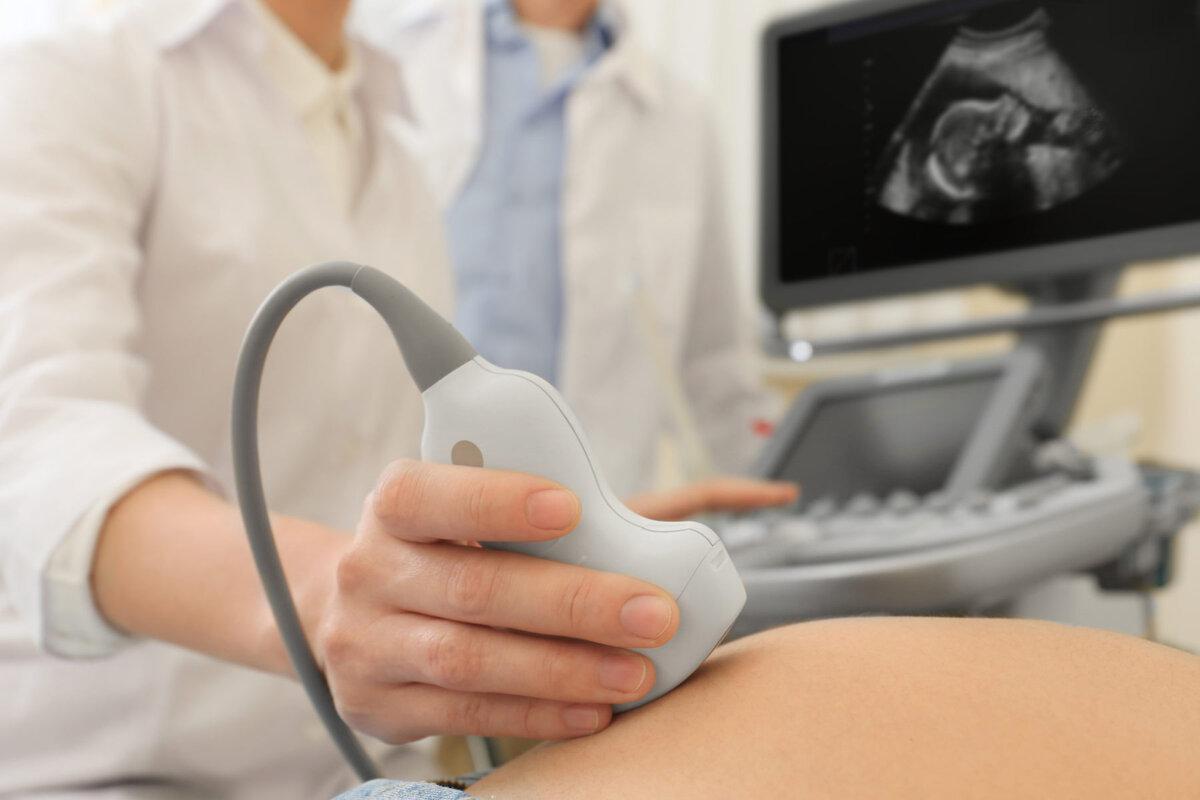

The Well-knowledgeable Sonographers of the Best Diagnostic Centre in Siliguri use Advanced Machines to delineate organs or areas in a patient's body.